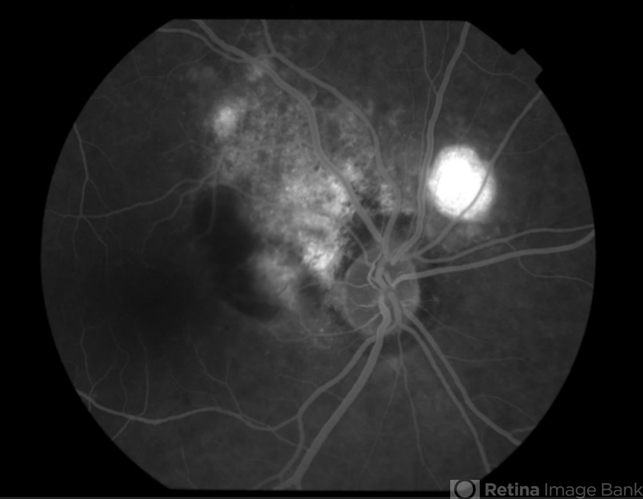

- Polypoidal Choroidal Vasculopathy

- polypoidal choroidal vasculopathy (PCV), idiopathic polypoidal choroidal vasculopathy

- Angiography revealed peripapillary hyperfluorescence with mild late leakage, as well as blockage by the subretinal hemorrhage noted clinically.